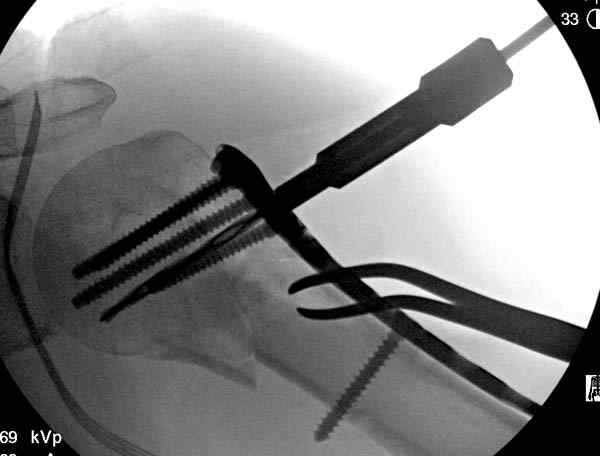

После устранения смещения пластина установлена выше (5,6,7) и финальные снимки (8,9,10)

Подбор импланта тоже имеет значение, например многие импланты направлены для фиксации перелома без учета ротаторной манжетки. Предпочтительными являются низко сидящие полиаксиальные пластины, где верхние шурупы можно проводить под углом  в 120 градусов. (11)